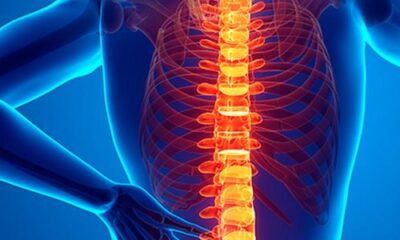

A nova técnica é uma evolução da cirurgia tradicional Segundo a Organização Mundial da Saúde (OMS), 80% da população teve ou terá dor na coluna em...